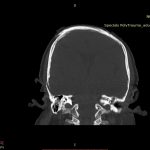

Examinare de rutină cerebrală, nativ și cu substanță de contrast (SDC) pentru diagnosticul:

- Accidentelor vasculare cerebrale ischemice sau hemoragice

- Tumorilor cerebrale

- Evaluarea deplasării liniei mediane

- Evaluarea cisternelor perimezencefalice

- Diagnosticul edemului cerebral, a contuziei cerebrale, a leziunilor axonale difuze edematoase/hemoragice, a dilacerării cerebrale, a hematomului intraparenchimatos posttraumatic, a hematoamelor subdurale/extradurale (acute, subacute, cronice), a hemoragiei intraventriculare, a hemoragiei subarahnoidiene